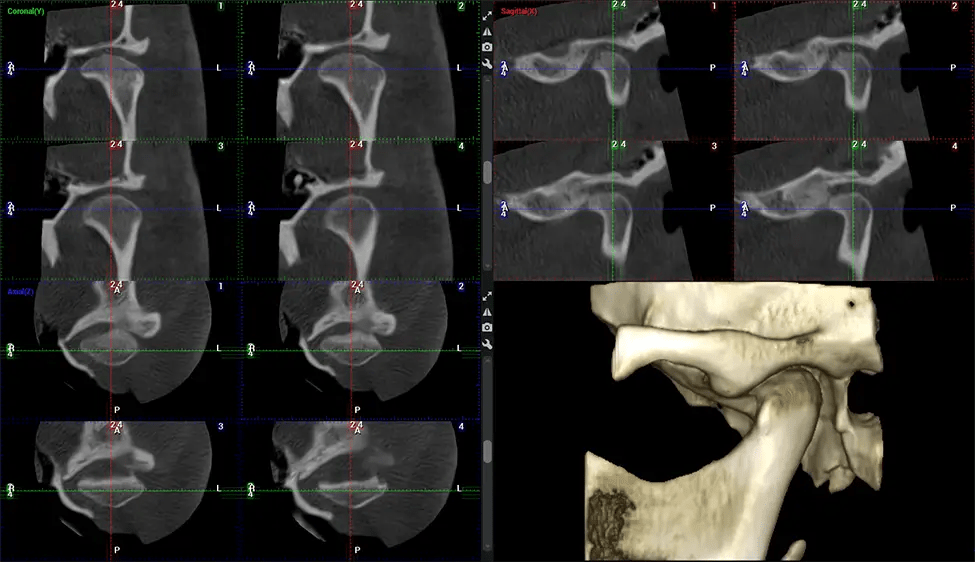

Orthodontist Assessing facial asymmetry, planning orthognathic surgery, and managing cleft lip and palate and sleep apnea. Provides a comprehensive view of the craniofacial complex to better plan treatments and evaluate outcomes.

Upper Cervical Chiropractor Diagnosing structural problems in the C1-C2 vertebrae, assessing misalignment and instability, and evaluating chronic pain. Enables precise, weight-bearing views of the upper cervical spine, helping to identify abnormalities that inform targeted, non-invasive therapies.

ENT Physician Diagnosing obstructive sleep apnea (OSA) and evaluating sinus and nasal cavity anatomy. Visualizes the entire pharyngeal airway to measure volume, pinpoint constrictions, and plan corrective surgery if needed.